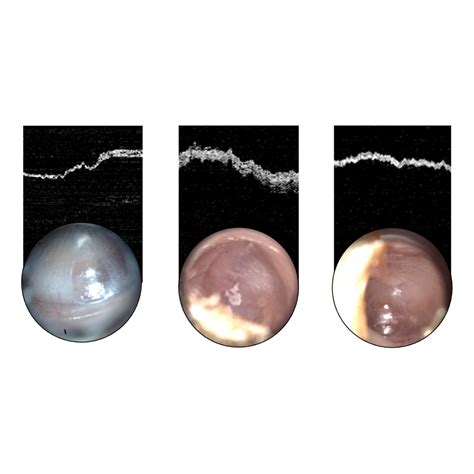

Otoscope Inside Ear

Have you ever felt a persistent itch, blockage, or discomfort in your ear and wondered exactly what is happening deep inside the canal? In the past, answering this question required an expensive visit to a doctor. However, modern technology has brought the clinical utility of an otoscope inside ear examination directly into the comfort of your own home. By utilizing a high-definition digital otoscope, individuals can now visualize the ear canal and tympanic membrane (eardrum) with remarkable clarity, allowing for better monitoring of ear health and hygiene.

• pictures of eardrum through otoscope